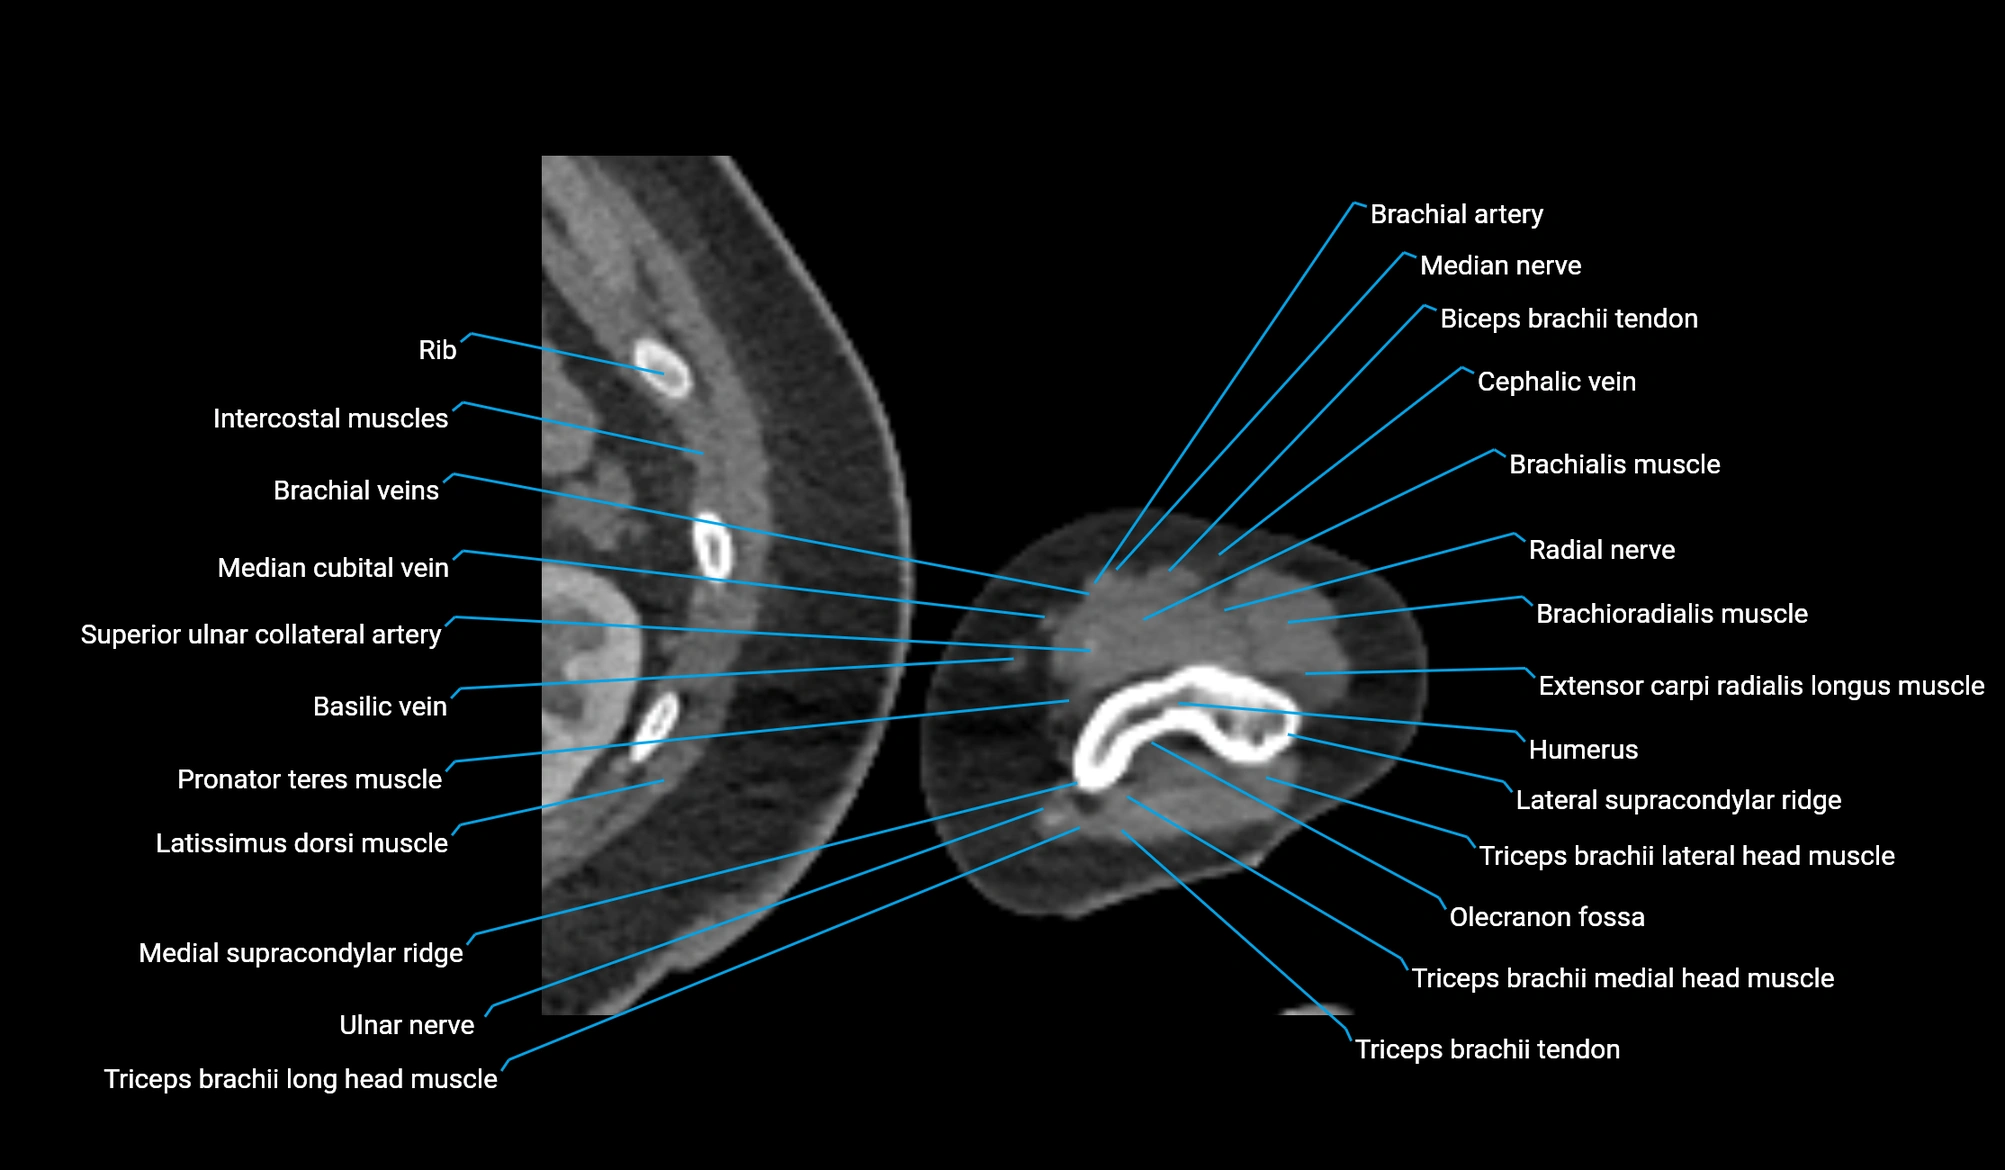

- Brachial artery

- Brachialis muscle

- Brachioradialis muscle

- Cephalic vein

- Extensor carpi radialis longus muscle

- Lateral head of triceps brachii muscle

- Lateral supracondylar ridge

- Long head of triceps brachii muscle

- Medial head of triceps brachii muscle

- Medial supracondylar ridge

- Median cubital vein

- Median nerve

- Olecranon fossa

- Pronator teres muscle

- Radial nerve

- Superior ulnar collateral artery

- Triceps brachii tendon